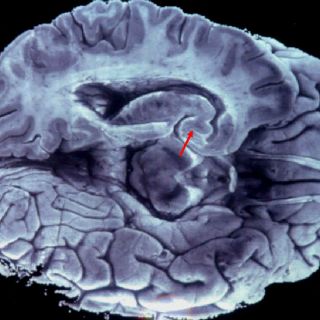

WASHINGTON, ESTADOS UNIDOS (14/MAR/2016).- Un grupo de científicos ha descubierto cómo determinadas células del

cerebro computan la longitud del sonido y detectan los sonidos cortos, según un estudio publicado hoy en la revista Proceedings of the National Academy of Sciences.